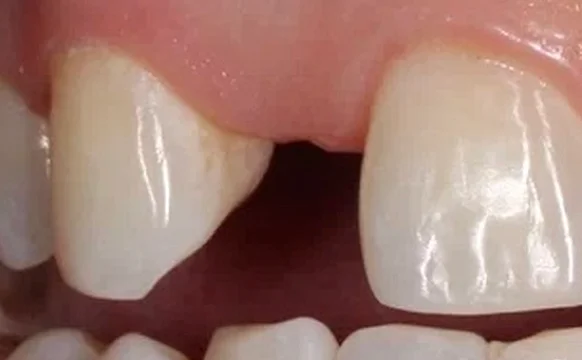

Имплантация передних зубов

Восстановление передних зубных единиц — сложная процедура, позволяющая восстановить природную красоту и здоровье улыбки.

Проблема

отсутствие зуба